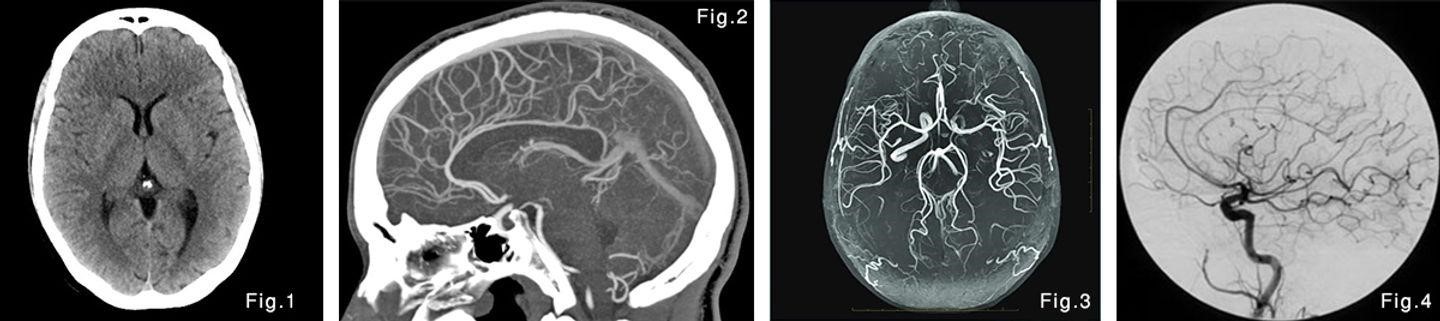

კომპიუტერული ტომოგრაფია (კტ) არის, როგორც წესი პირველი კვლევა, რომელიც გამოიყენება ტვინში სისხლდენის დასადგენად (სურ 1).

კტ-ანგიოგრაფიას მეშვეობით შესაძლებელია სისხლძარღვების დეტალური სურათის ნახვა და ანევრიზმის არსებობის შემთხვევაში მისი ლოკაციის, ზომის და ფორმის შეფასება (სურ 2).

მაგნიტურ-რეზონანსულ ტომოგრაფია (მრტ) ასევე აჩვენებს, არის თუ არა სისხლდენა თავის ტვინში. მრტ-ს ტიპი, რომელიც დეტალურად იკვლევს სისხლძარღვებს, ეწოდება მრ-ანგიოგრაფია (ნახ 3). ამ კვლევასაც, უმეტეს შემთხვევაში შეუძლია გამოავლინოს ანევრიზმის არსებობა, მისი ზომა და ფორმა.

ციფრული სუბტრაქციული ანგიოგრაფია იძლევა თავის ტვინის სისხლძარღვების ყველაზე დეტალურ სურათს (სურ. 4). პროცედურა გულისხმობს კათეტერის შეყვანას საზარდულის არტერიიდან თავის ტვინის სისხლძარღვებში და შემდეგ სპეციალური სარენტგენო კონტრასტის შეყვანას.